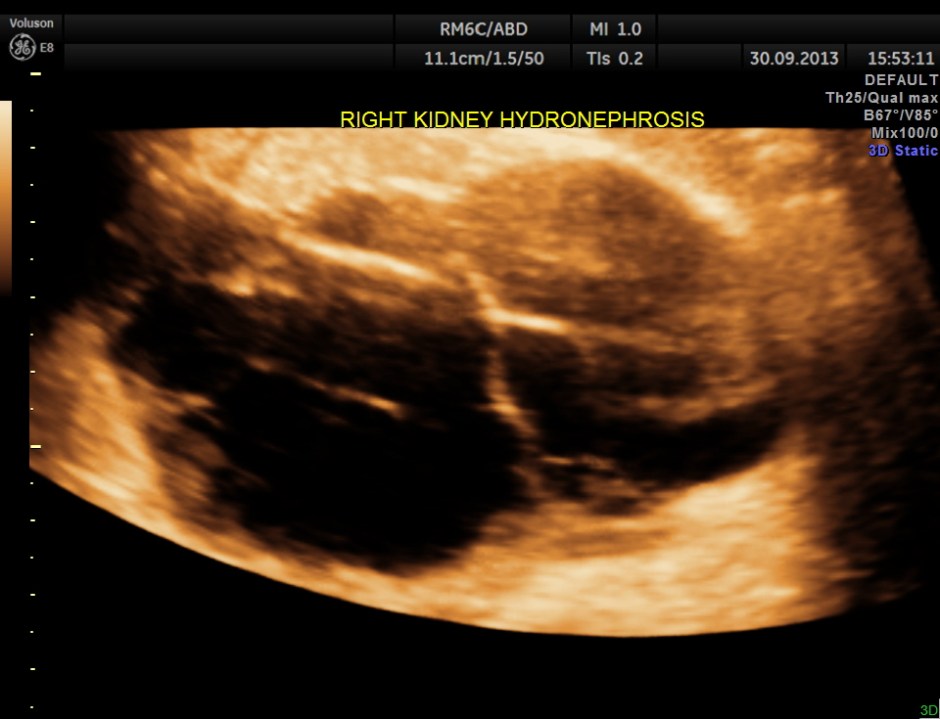

the right kidney showed moderate to severe hydro-nephrosis

the following images show the 2 d and 3 d appearance of the same.

The diagnosis given was Large calculus in the urinary bladder , Severe prostatic enlargement with prominent median lobe hypertrophy , causing Right sided obstructive uropathy.

The diagnosis was made with the 2D images , but the 3 D images were very helpful in explaining to the patient.